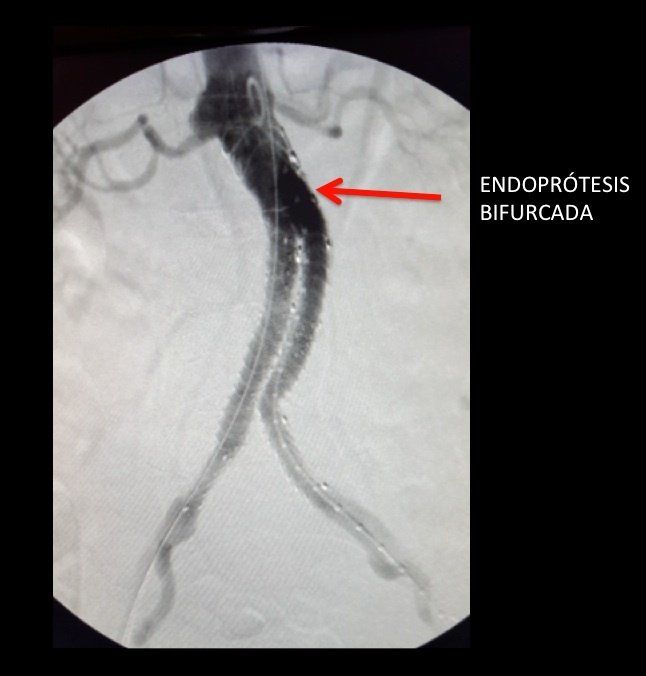

Hoy en día disponemos de diversas opciones terapéuticas, y escogeremos la mejor cada caso en función de una decisión individualizada. La cirugía convencional sigue teniendo sus indicaciones; en ella se procede a una reparación abierta del aneurisma sustituyendo el tramo enfermo por una prótesis. Pero hoy en día hay más motivos para decantarnos por una técnica endovascular, en la que una endoprótesis navega por dentro de las arterias hasta colocarla en su sitio; esto nos permite reducir enormemente la agresividad del procedimiento así como los días de ingreso y la recuperación final, aunque obliga a un seguimiento más estricto. Existen además procedimientos híbridos que combinan ambas técnicas.